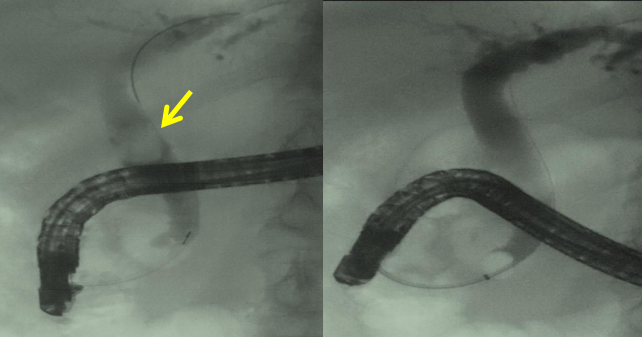

手术当天,尽管患者脆弱的心功能给麻醉带来极大的挑战,但经验丰富的麻醉科副主任王俊教授带领王爽医生迎难而上,有条不紊为患者实施麻醉诱导、插管全身麻醉,术中通过动脉穿刺实时精确监测血压,确保患者生命体征平稳。在麻醉科的有力保障下,ERCP手术团队通过激光碎石结合机械碎石的方式进行处理。但意外发现,部分碎石嵌顿于左肝内胆管起始部,常规DSA下导丝反复尝试均无法进入左肝内胆管取石。关键时刻,团队启动术前制定的应急预案,采用胆道子镜直视下超选左肝内胆管,成功后沿导丝置入取石网篮及取石球囊,逐步将碎石取出。经过2个多小时的艰苦奋战,嵌顿的胆管结石被彻底清除。

左图箭头所指为嵌顿胆管结石,中图箭头所指为子镜下嵌顿胆管结石,右图为子镜下激光碎石